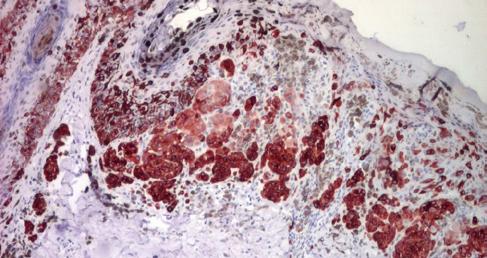

• Examen histopatologic care evidențiază rata mitotică, infiltratul inflamator peritumoral, indice Breslow, nivelul de invazie Clark;

• Imunohistochimie: markeri S100, HMB45 etc.